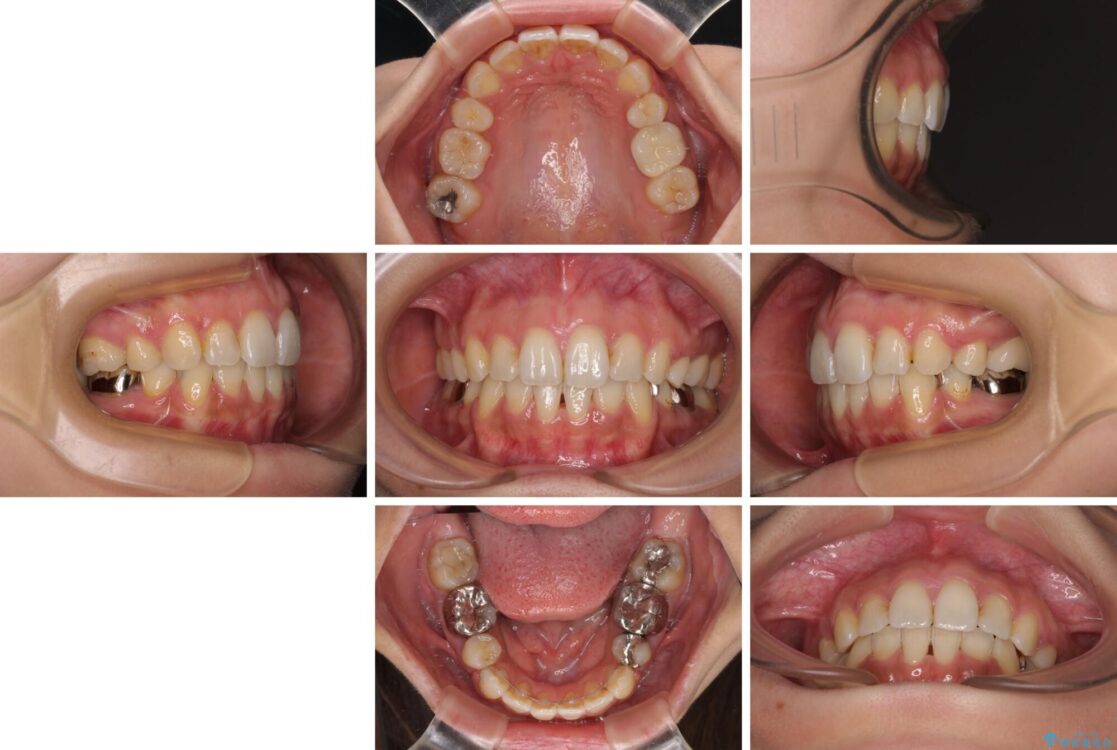

治療前

• デコボコと口元の突出感 ハーフリンガルでの抜歯矯正 治療前画像

前歯のデコボコと上顎の前突感による口の閉じにくさを気にして来院された患者様です。

治療計画

目立たない装置を希望されたので、上顎が裏側装置のハーフリンガルを選択し、上下左右の小臼歯(計4歯)を抜歯して矯正治療を行うこととしました。